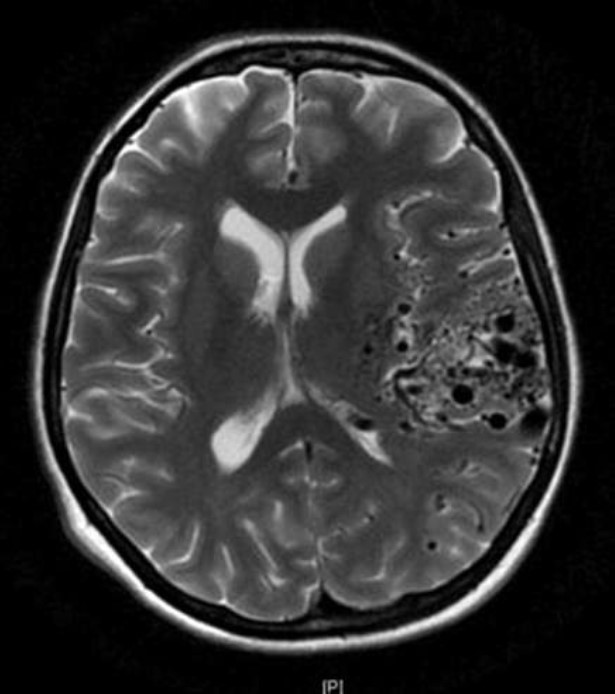

A 25-year-old woman presents with a history of left arm automatisms and lip smacking, followed by a generalized convulsion. Her history is also remarkable for recurring headaches previously attributed as migraines. An axial magnetic resonance image (MRI) is shown. Which of the following is considered the most likely diagnosis?

AVMs are arteriovenous connections without capillary networks, usually with gliotic brain tissue within the AVM. These often present with hemorrhages, headaches, or seizures. Typically, AVMs are observed if unruptured, but several factors are taken into consideration when determining whether or not to intervene: age, surgical risk, location, gender, and lifetime hemorrhage risk. Treatment options include surgical resection, radiosurgery, endovascular embolization, or a multimodal approach (especially if >3 cm)

Arteriovenous malformation